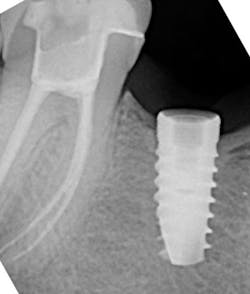

There are many different types of screw/implant retrieval and rescue kits made by different companies. Nobel Biocare, Neobiotech, Osstem (OssVK), BTI Biotechnology Institute, and Salvin Dental Specialties all make these types of kits. The author has found great success with screw retrieval using the Implant Rescue Kit from Salvin Dental (figure 3). This kit is especially useful when the broken screw is fractured in the apical 50% of the implant chamber (figure 4). Following are the steps involved in using this implant screw retrieval kit (figure 5).